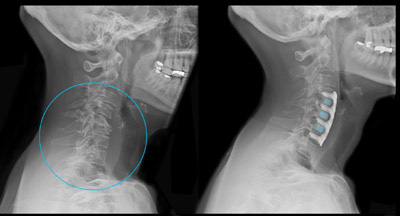

The Degenerative Disc Disease Treatment Market can be segmented based on surgery type as spinal fusion, artificial disc replacement, decompression, fixation and motion preservation. Among these, spinal fusion surgery accounted for the largest share of the market in 2024. Spinal fusion is considered as the standard treatment procedure for degenerative disc disease as it helps stabilize the damaged vertebral segment and provides reliable pain relief. It usually involves fusing two or more vertebrae together to eliminate pain caused by pressure on spinal nerves.